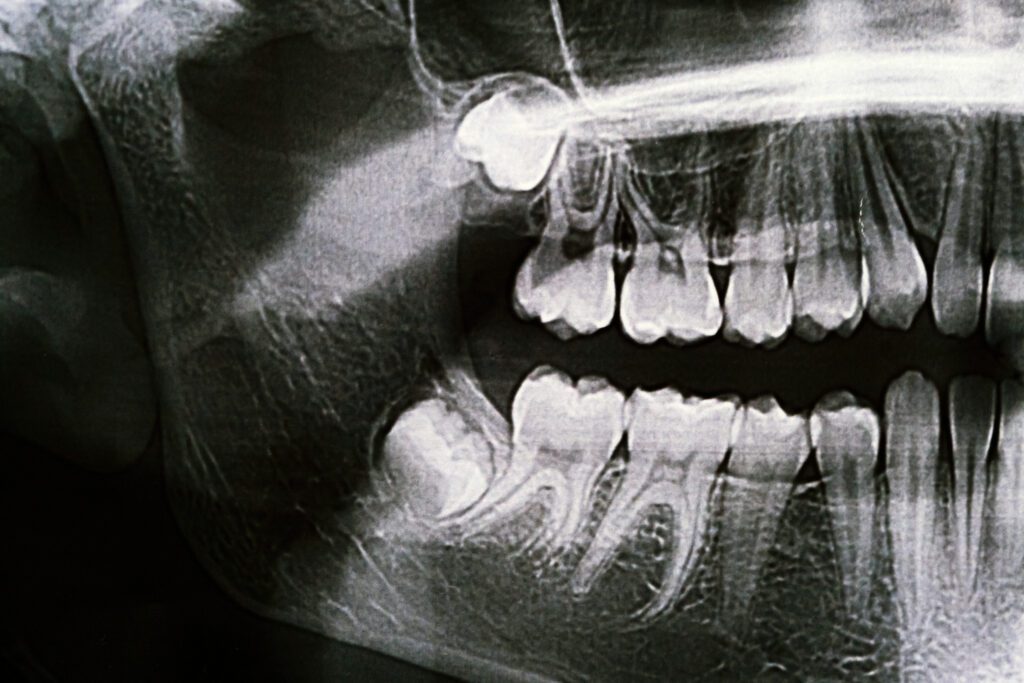

The average adult mouth is designed to hold around 28 teeth comfortably, but most adults end up with 32. The additional four teeth are called wisdom teeth or third molars. When there isn’t enough room for them, the wisdom teeth become blocked or impacted by the other teeth around them. This can become extremely traumatizing. If the wisdom tooth partially erupts, food can get trapped in the tissue surrounding it, which can lead to bacterial growth and possibly serious infection.

By removing wisdom teeth when a patient is a young adult, Dr. Barbat is able to prevent potential healing problems. When a person reaches the age of their mid-thirties, there are much higher risks involved in wisdom teeth removal. The best time to remove wisdom teeth is generally between the ages of fifteen to eighteen.